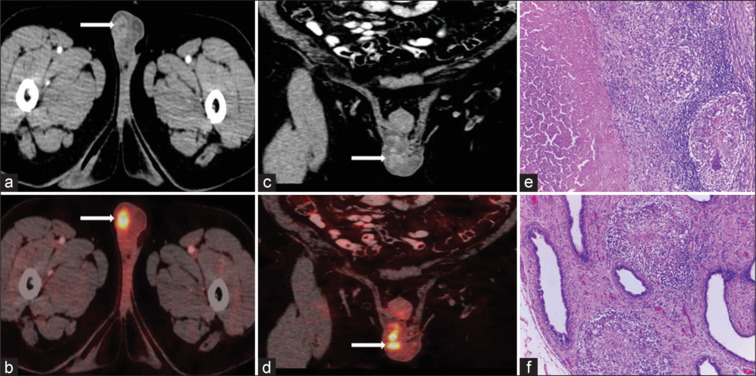

Bacillus Calmette-Guërin (BCG) has been traditionally used as a vaccine against tuberculosis (TB), which contains live, attenuated strain of Mycobacterium bovis. However, intravesical BCG administration has been used as an immunological treatment of superficial bladder cancer. Complications after bladder instillation of BCG are rare. We report a case of carcinoma urinary bladder with histopathologically proven granulomatous epididymo-orchitis (TB) after treatment with intravesical BCG.